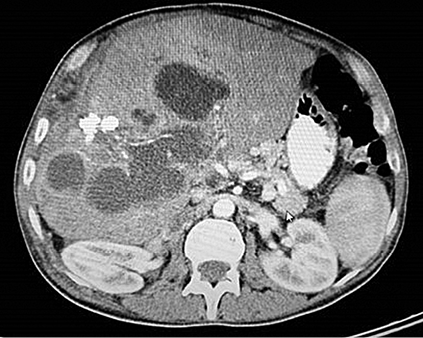

The patient underwent surgery and the hydatid cysts located in the right lobe of the liver were unroofed and the inner surface was rinsed with savlon solution. Afterwards, anterior and posterior parts of the left portal vein were examined. The parenchyma of the liver was incised and thrombotic right and middle hepatic veins were ligated. Right hepatectomy was performed over caval vein. The lumen of the portal vein was opened and no portal blood flow was seen (Figure 2).

Figure 2. Thrombosed portal vein

The portal vein was catheterized and excessive amount of sister vesicles came out after the irrigation. However, no blood flow was detected with Doppler evaluation. The wall of the portal vein is repaired and other cystic lesions inside the liver parenchyma were emptied.

Figure 3. Pathology specimen